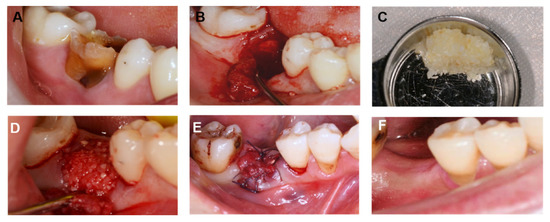

4. Case Report